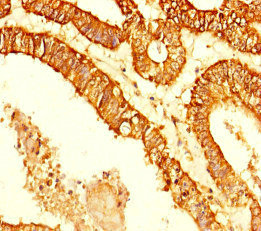

Immunohistochemistry of paraffin-embedded human endometrial cancer using CSB-PA872489HA01HU at dilution of 1:100